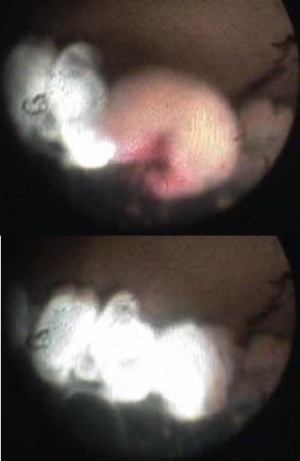

One of the great advantages of ECP over transscleral cyclophotocoagulation techniques is the ability to deliver laser energy in a highly titratable fashion to the ciliary processes. The optimum tissue effect is to whiten the ciliary process and effect visible tissue shrinkage. Photocoagulation is applied with the endoscope 1.0–3.0 mm from the ciliary processes. Kahook, Noecker, and colleagues recommend lasering with a distance of about 2 mm from the ciliary processes. From this distance one can usually see 6 ciliary processes in the field of view of the endoscope (see corresponding figure to right). This distance is ideal for minimizing laser energy transmission loss while also minimizing the risk of overtreatment.[12] The power levels of the 810-nm semiconductor diode laser are titrated upward from lower power levels to achieve whitening and shrinkage of the ciliary processes (see corresponding figure to right). Usually 100-300 mW is all that is required to achieve the desired effect on tissues. A slow continuous wave application of the laser treatment allows surgeons to methodically “paint” the entirety of each ciliary process in a smooth, well-controlled fashion. Treatment of at least 270° is often required to get optimal intraocular pressure reduction with ECP.[13] If administering ECP through one incision, the curved endoscope probe enhances a surgeon’s ability to expand the ciliary process treatment area beyond what can be accomplished with a straight endoscope. Kahook and colleagues showed that 360 degrees of treatment with ECP through two incisions is superior to partial treatment through one incision. 360 degree treatment produced lower IOP, gave greater reduction in glaucoma medication burden, and had fewer treatment failures than partial treatment.[13]